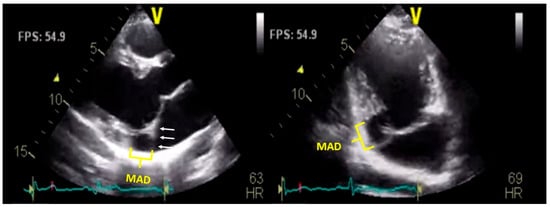

4.1. Transthoracic Echocardiography (TTE)

- Konda, T.; Tani, T.; Suganuma, N.; Nakamura, H.; Sumida, T.; Fujii, Y.; Kawai, J.; Kitai, T.; Kim, K.; Kaji, S.; et al. The analysis of mitral annular disjunction detected by echocardiography and comparison with previously reported pathological data. J. Echocardiogr. 2017, 15, 176–185. [Google Scholar] [CrossRef]

- Carmo, P.; Andrade, M.J.; Aguiar, C.; Rodrigues, R.; Gouveia, R.; Silva, J.A. Mitral annular disjunction in myxomatous mitral valve disease: a relevant abnormality recognizable by transthoracic echocardiography. Cardiovasc. Ultrasound 2010, 8, 53. [Google Scholar] [CrossRef]